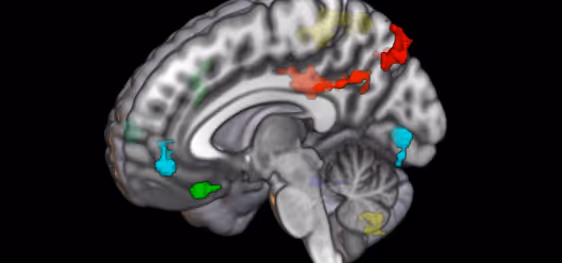

The Hurd Lab uses state-of-the-art technology to analyze human and animal tissues. Additionally, we use non-invasive neuroimaging techniques such as PET, MRS, fMRI, and small animal MRI to determine real-time changes in neural activity, neurotransmitter levels, and drug distribution, as well as structural changes in the brain. We pioneered DREADD-assisted metabolic mapping (DREAMM), a technique combining molecular pharmacogenetic and in vivo imaging strategies to provide high-resolution quantitative mapping of functional brain circuits associated with disturbance of genes expressed in specific cell populations.